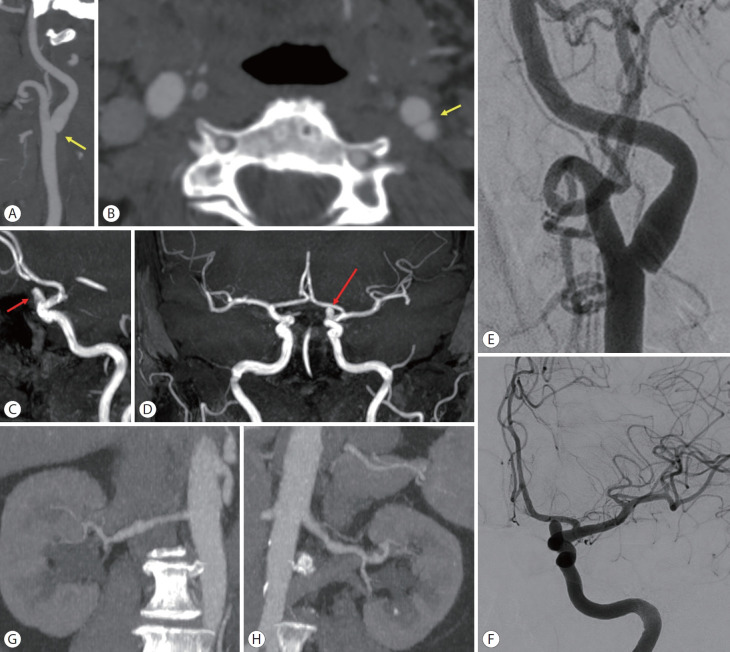

颈动脉网在50多年前被描述为非典型纤维肌肉发育不良(FMD)亚型,并有高度支持的病理证据作为内膜FMD。在接下来的几十年里,从导管血管造影或数字减影血管造影(DSA)到无创成像技术的转变以及病理程序的急剧减少导致了这些信息的逐渐丢失。目前,由于颈动脉网与隐源性缺血性脑卒中的关系,人们对其的关注有所增加。事实上,潜在的假设是颈动脉网的形态特征可能决定了动脉对动脉栓塞的血栓形成潜力。颈动脉网的病理允许识别嵌入在网袋中的小血栓,并且从颅内动脉血管内取出的血栓的特征非常相似。颈动脉网的诊断通常采用非侵入性技术,如计算机断层血管造影、超声和磁共振成像,需要两种不同技术的一致性来确认诊断。在诊断不确定的情况下,当考虑介入治疗缺血性中风或颈动脉网时,通常考虑DSA。有症状病例的治疗选择包括药物治疗(单或双抗血小板)或介入治疗(手术或支架置入术),但没有关于治疗的随机对照试验。本综述的主要目的是介绍目前关于颈动脉网的知识,检索FMD的历史数据和血管造影分类,并讨论在症状病例中与卒中相关的生物学合理性,以及更新FMD分类的必要性,以及前瞻性数据。

Carotid web was described more than 50 years ago as an atypical fibromuscular dysplasia (FMD) subtype with highly supporting pathological evidence as intimal FMD. In the following decades, the transition from catheter angiography or digital subtraction angiography (DSA) to non-invasive imaging techniques and the dramatic decrease in pathological procedures contributed to the gradual loss of this information. Currently, attention on the carotid web has increased due to its association with cryptogenic ischemic stroke. In fact, the underlying hypothesis is that the morphological features of the carotid web may determine a thrombogenic potential with artery-to-artery embolism. The pathology of the carotid web allowed identification of small thrombi embedded in the web pouch, and the features of thrombi endovascularly retrieved from intracranial arteries are very similar. The diagnosis of carotid web is usually made by non-invasive techniques, such as computed tomography angiography, ultrasound, and magnetic resonance imaging, requiring the concordance of two different techniques for confirming the diagnosis. DSA is usually considered in cases of diagnostic uncertainty and when interventional treatment of ischemic stroke or carotid web is considered. Treatment options in symptomatic cases include medical therapy (single or dual antiplatelets) or interventional approach (surgery or stenting), but there are no randomized controlled trials about therapy. The main aim of this review is to present the current knowledge on carotid web, retrieving historical data and angiographic classifications of FMD, as well as to discuss the biological plausibility of the association with stroke in symptomatic cases and the need for an updated classification of FMD, together with prospective data.